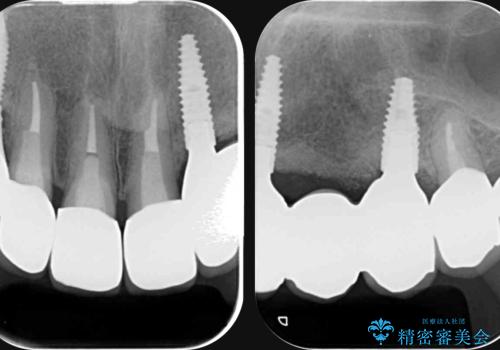

抜去を行ったのち、インプラント治療を計画しますが骨量が少ないため、まず骨の造成を行ったのちインプラントを埋入していく治療計画としました。

- 99万円(インプラント×2・アバットメント×2・ジルコニアクラウン×2・骨造成)費用は治療当時の料金となります

インプラント治療を行ったことでしっかりとした咬合関係を確立することができました。